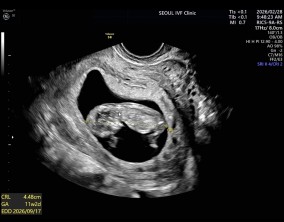

임신 수치 16, 9주차 기적의 기록

서울IVF에서는 단순히 배아 생성과 이식만 해주시는 것이 아니라, 제 생활 전반까지 신경 써주셨습니다. 휴식기에도 그저 기다리는 것이 아니라 항노화에 도움이 되는 링겔을 처방…